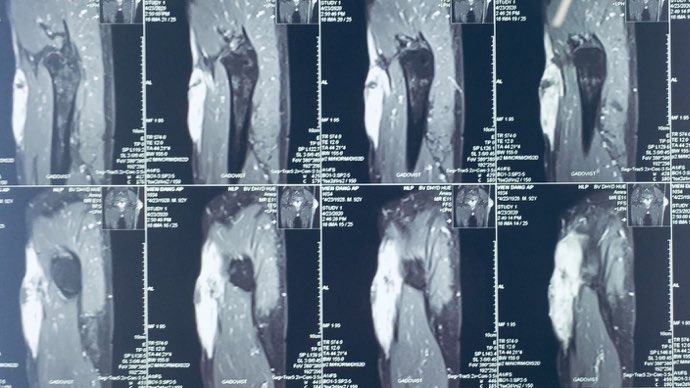

Bước đầu sử dụng Ligasure trong phẫu thuật đầu mặt cổ tại Khoa Tai Mũi Họng Bệnh viện Trường Đại học Y Dược Huế

Tiến sĩ, Bác sĩ Phan Hữu Ngọc Minh Giảng viên Bộ môn Tai Mũi Họng Khoa Tai Mũi Họng, Bệnh viện Trường Đại học Y Dược Huế